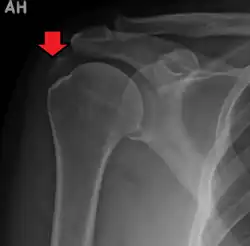

A plain X ray of the shoulder showing calcific tendinitis

Calcific tendinitis is a common condition where deposits of calcium phosphate form in a tendon, sometimes causing pain at the affected site. Deposits can occur in several places in the body, but are by far most common in the rotator cuff of the shoulder. Around 80% of those with deposits experience symptoms, typically chronic pain during certain shoulder movements, or sharp acute pain that worsens at night. Calcific tendinitis is typically diagnosed by physical exam and X-ray imaging. The disease often resolves completely on its own, but is typically treated with non-steroidal anti-inflammatory drugs to relieve pain, rest and physical therapy to promote healing, and in some cases various procedures to breakdown and/or remove the calcium deposits.

Calcific tendinitis is typically diagnosed by physical examination and X-ray imaging.[1] During the formative phase, X-ray images typically reveal calcium deposits with uniform density and a clear margin.[1] In the more painful resorptive phase, deposits instead appear cloudy and with unclear margins.[1] By arthroscopy, formative stage deposits appear crystalline and chalk-like, while resorptive stage deposits appear smooth resembling toothpaste.[1] Ultrasound is also used to locate and assess calcium deposits. In the formative stage, deposits are hyperechoic and arc-shaped; in the resorptive stage deposits are less echogenic and appear fragmented.[1][3]